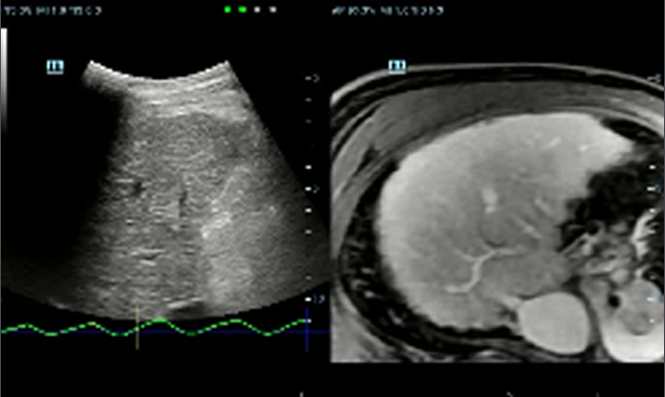

Dzi?ki technologii ZST+oraz Plane Waves, funkcja HiFR CEUS umo?liwia ultraszybk? wizualizacj? struktury naczyniowej i charakteru perfuzji w fazie t?tniczej.; mo?e s?u?y? jako narz?dzie uzupe?niaj?ce dla funkcji?UWN+

Przypadek kliniczny z wykorzystaniem technologii HiFR CEUS: Ogniskowy rozrost guzkowy w?troby

*?Nie zaleca si? stosowania HiFR CEUS w fazie p├│?nej lub na g??boko?ci 10 cm